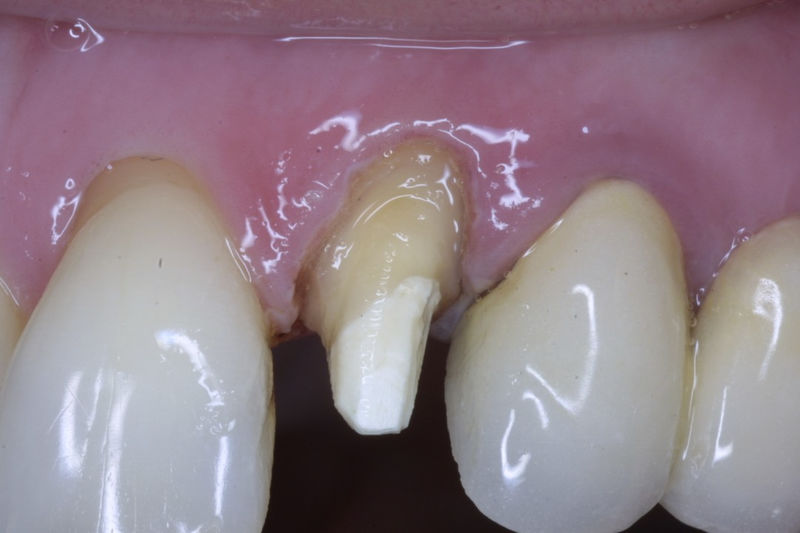

La restauración de un diente tras una endodoncia, es crucial para su supervivencia a largo plazo, ya que el procedimiento puede debilitar la estructura dental. El tipo de restauración elegido depende principalmente de la cantidad de estructura dental remanente después de la endodoncia. Principalmente se usan incrustaciones, coronas y/o postes.

Son aditamentos artificiales colocados en la parte interna de la raíz de dientes con tratamiento endodóntico y con amplia destrucción. Usados comúnmente para soportar coronas completas.

Disciplina fundamental de la Odontología enfocada en el diagnóstico, prevención y tratamiento restaurador de las piezas dentales que han sufrido daños. Su objetivo principal es devolver al diente su equilibrio biológico, funcional y estético cuando su integridad ha sido alterada. Resinas directas, incrustaciones, coronas.